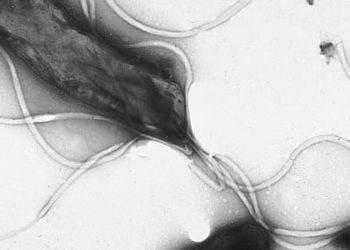

Image: PD/Yutaka Tsutsumi, M.D. 1. Individuals with increased expression of Toll-Like Receptor 1 (TLR-1) were more likely to be seropositive ...